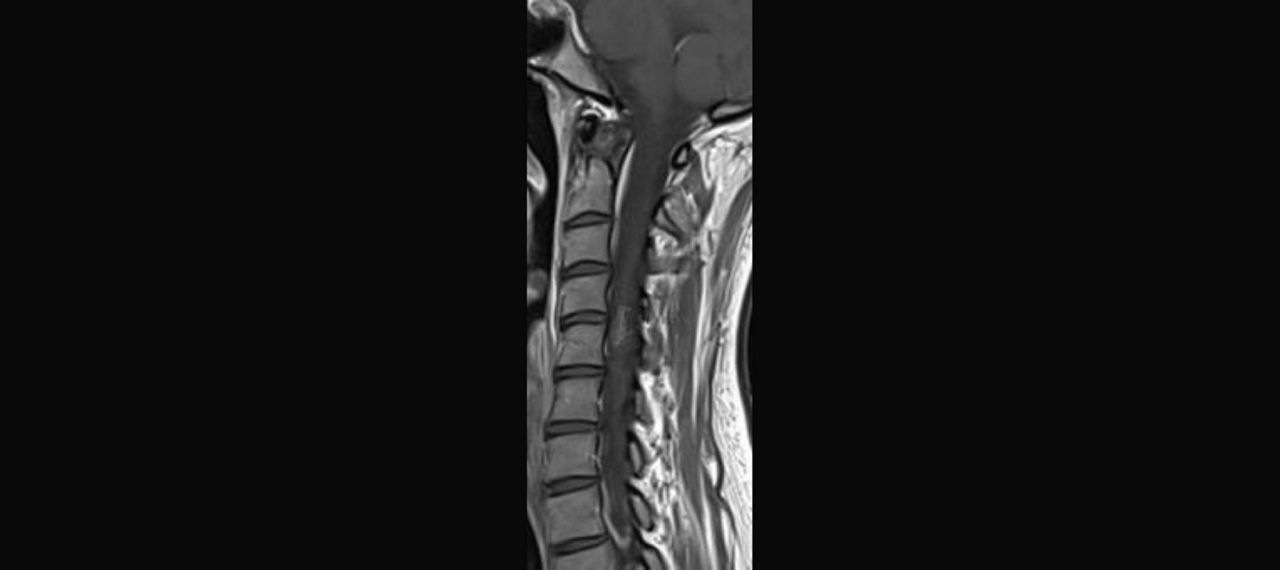

Abb. 1: Bei Vorstellung großflächige Läsion

Abb. 2: Leichte Besserung

Abb. 3: Nach 2 Monaten: Ausweitung der flächigen Läsionen mit zystischen Anteilen

Abb. 4: Nach 2 Monaten

Abb. 5: Nach 2 Monaten; perlschnurartige kontrastmittelaufnehmende Herde über das gesamte Myelon

Abb.6: 4 Monate nach Vorstellung: Zunahme der flächigen Marklage-Läsionen und der zystischen Defekte